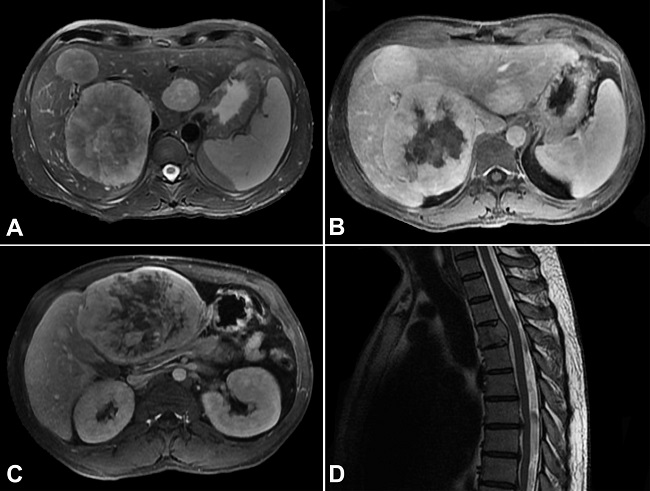

Imaging studies documented more than ten liver nodules, the largest in segments III (12.5 x 9.3 cm) and VII/VIII (11.2 x 8.8 cm), and osteolytic lesions in the vertebral bodies of D4 and L3, suggestive of metastases (Figure 2). Percutaneous liver biopsy confirmed hepatic metastases of SFT (Figure 3).